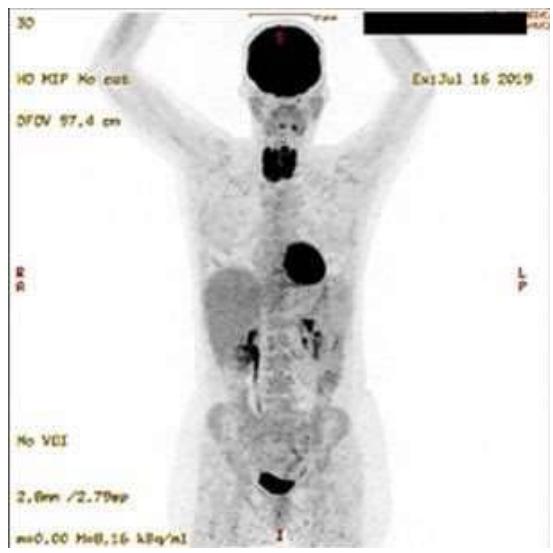

Through a series of observational studies on the pathogenesis of benign thyroid disease we were able to deduce in 2021 that the central pathogenetic mechanism was a condition of glycolytic metabolism as evidenced through combined diagnostic imaging with 3D-power Doppler sonography and positron emission tomography (PET) using $^{18}\mathrm{F}$ -fluorodeoxyglucose ( $^{18}\mathrm{F}$ -FDG) (Figure 6 in (1)). In the $^{18}\mathrm{F}$ -FDG study both the thyroid and the heart displayed an intense tracer uptake (Figure 1), an association never commented before in the literature (2). Since the innate capability of desoxyglucose is to indicate glycolysis (3), we interpreted the image as an in-vivo depiction of this metabolic process which correlated with increased vascularity. Given that patients with benign thyroid disease frequently have low levels of coenzyme $\mathsf{Q}_{10}$ ( $\mathrm{CoQ}_{10}$ ) and that experimental $\mathrm{CoQ}_{10}$ deficiency is linked to hypoxia as shown by Liparulo et al., in 2021 (4), our current interpretation of the diagnostic image shown below is that it represents glycolysis and is related to conditions of hypoxia. In Liparulo's experiment with the human T67 glioma cell line, $\mathrm{CoQ}_{10}$ deficiency was produced by inhibiting its biosynthesis using the competitive inhibitor 4-nitrobenzoate leading finally to low intracellular levels of oxygen, i.e., hypoxia (4).

Figure 1: $^{18}\mathrm{F}$ -FDG PET Study of a Patient with Recurrent Active Thyroiditis. Intense Tracer Uptake is Seen in the Thyroid and the Heart. The Brain Shows a Physiological Uptake. The renal pelvis, the ureters, and the urinary bladder depict the Physiological Excretion Path. Panel B Shows the Simple Pathogenetic Mechanism Leading to Hypoxia.